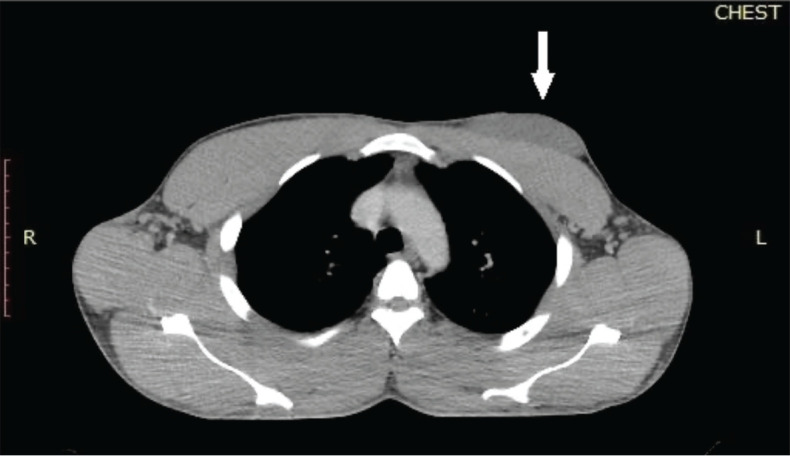

Dermatofibrosarcoma protuberans (DFSPs) is a low-grade mesenchymal tumour of dermal origin. Although lung metastasis is common, primary breast involvement is a very rare occurrence. The head and neck region, trunk and extremities are the common primary sites even though any site of the body may be potentially involved. Complete surgical resection with negative margins is the standard of care for nonmetastatic cases of DFSP. To the best of our knowledge, there have been no previous reports of metastatic DFSP of the breast to the lungs among male patients in sub-Saharan Africa. This case report presents data on a 32-year-old male with metastatic DFSP of the left breast to the lungs who was successfully treated with 800 mg daily imatinib mesylate therapy and achieved a complete radiological and clinical response after 1 year of palliative therapy.